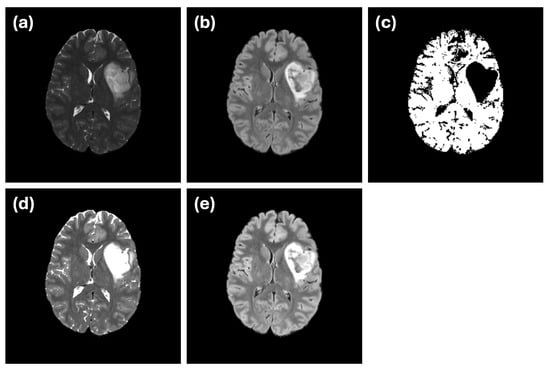

3.1. Image Dataset

4.1. Evaluation of Difference in MRI Sequences